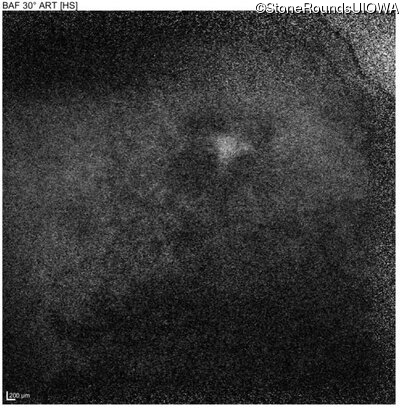

Blue Autofluorescence - Right - 20/100

Exemplar